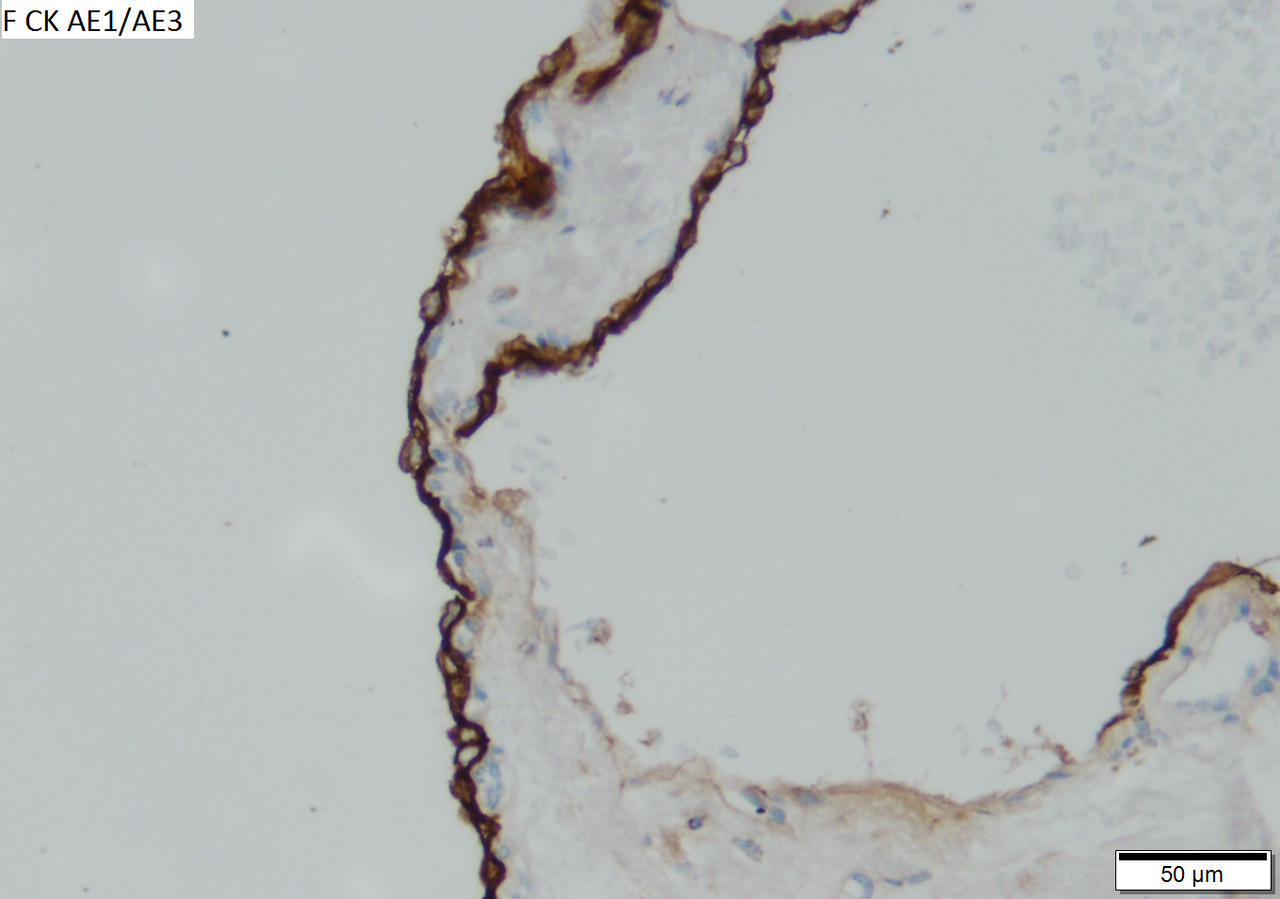

Microcystic serous cystadenoma of pancreas in a 62 year old woman. A. The tumor showed a central scar with multiple minute cysts; slight pressure yielded clear fluid. B. The mass comprises microcysts numberless. C. Cysts bear single cell linings with bland, amitotic nuclei. D. PAS without diastase shows positive cytoplasmic material. E. PAS with diastase shows the cytoplasmic material has been digested away. F. Keratin shows positive staining lining cells.